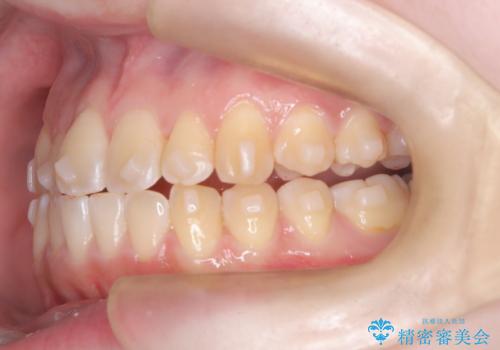

【インビザライン】オープンバイト。凸凹を治したい

- オープンバイトを主訴に来院されました。

インビザラインを用いIPRと遠心移動を行いオープンバイトと叢生の改善を行なっております。

前歯の叢生がわずかにありますが、追加アライナーの作成は希望されなかったため、歯を動かしていく動的治療は終了となりました。